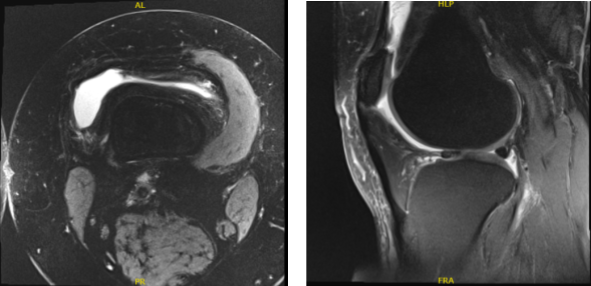

MRI results discussed and found out that there is moderate chondromalacia over the median ridge and medial facet of patella, with varying degrees of chondral surface fissuring and fraying.

Small joint effusion and lateral meniscus tear was also observed. By this time the patient decided to do rest and physical therapy and take naproxen and advised to return when no improvement happened.

MRI – Right Knee Non-Contrast